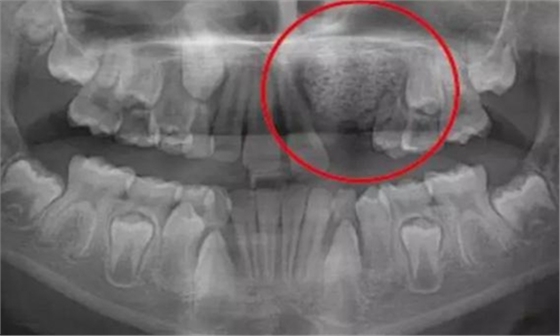

一名 23 區的9歲患者,在診所接受檢查時發現口內中存在大范圍含牙囊腫[圖1]。由于上頜竇下沿出現大范圍突出,迫切需要接受囊腫去除手術[圖2和3]。

術前全景片[圖1]